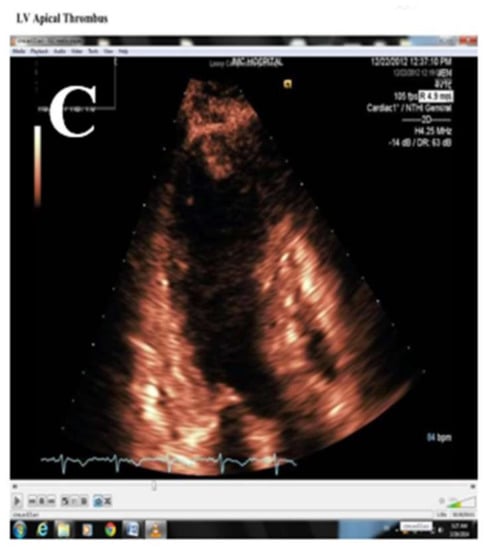

3.8. Thrombus and Prevention of Embolism in Patients with TTS